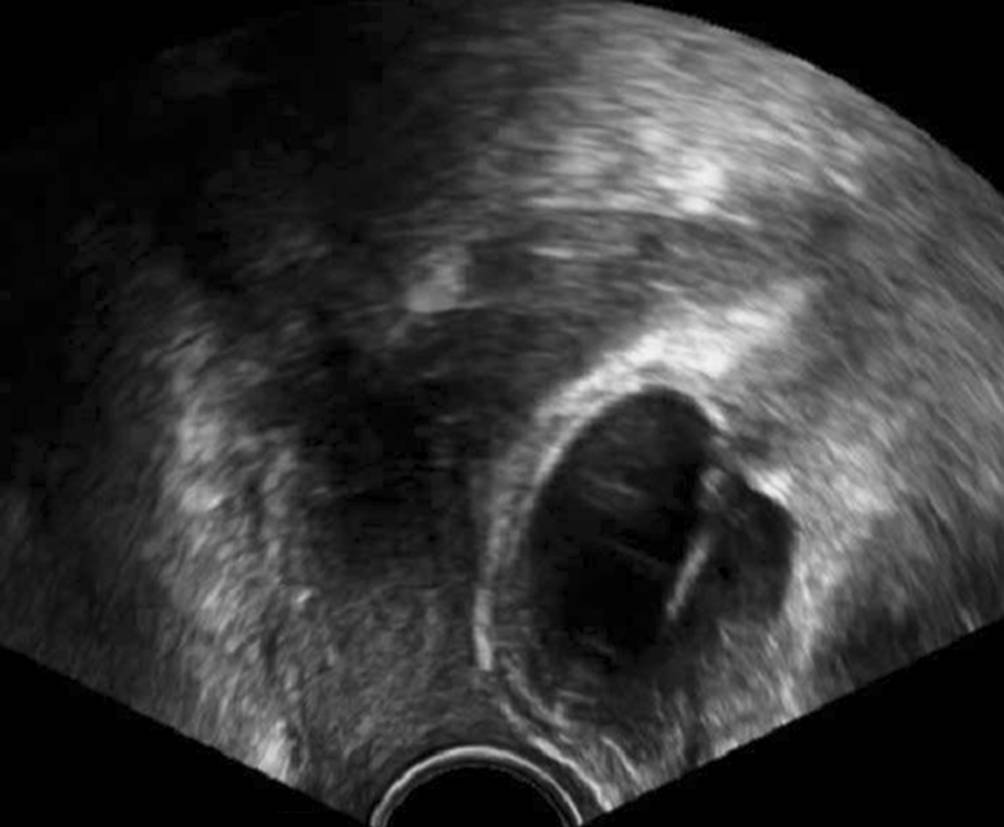

Artifizielle Sphinktere für Harn- oder Stuhlinkontinenz brauchen Depots, wobei ein mit physiologischer Kochsalzlösung gefülltes Ballonreservoir auch intraabdominal in unmittelbarer Nähe der Ovarien platziert werden kann (Abb. 3). Betroffene Patientinnen wissen darüber immer Bescheid, wenn man in den Unterlagen nichts findet, sollte man sie danach fragen. Vor allem sollte ein voreiliges Anpunktieren dieser Ballonreservoire – sei es aus diagnostischen Gründen, sei es, weil man es für einen Follikel hält – unterbleiben. Rücksprache mit Vertretern des Fachs, die üblicherweise solche Implantate legen, kann sehr aufschlussreich sein und Schaden für die Patientin verhindern.

Abb. 3

Das Reservoir eines Scott-Sphinkters (American Medical Systems, Minnetonka, MI, USA) kann unmittelbar neben den Ovarien liegen und sollte im Zuge reproduktionsmedizinischer Maßnahmen möglichst nicht anpunktiert werden